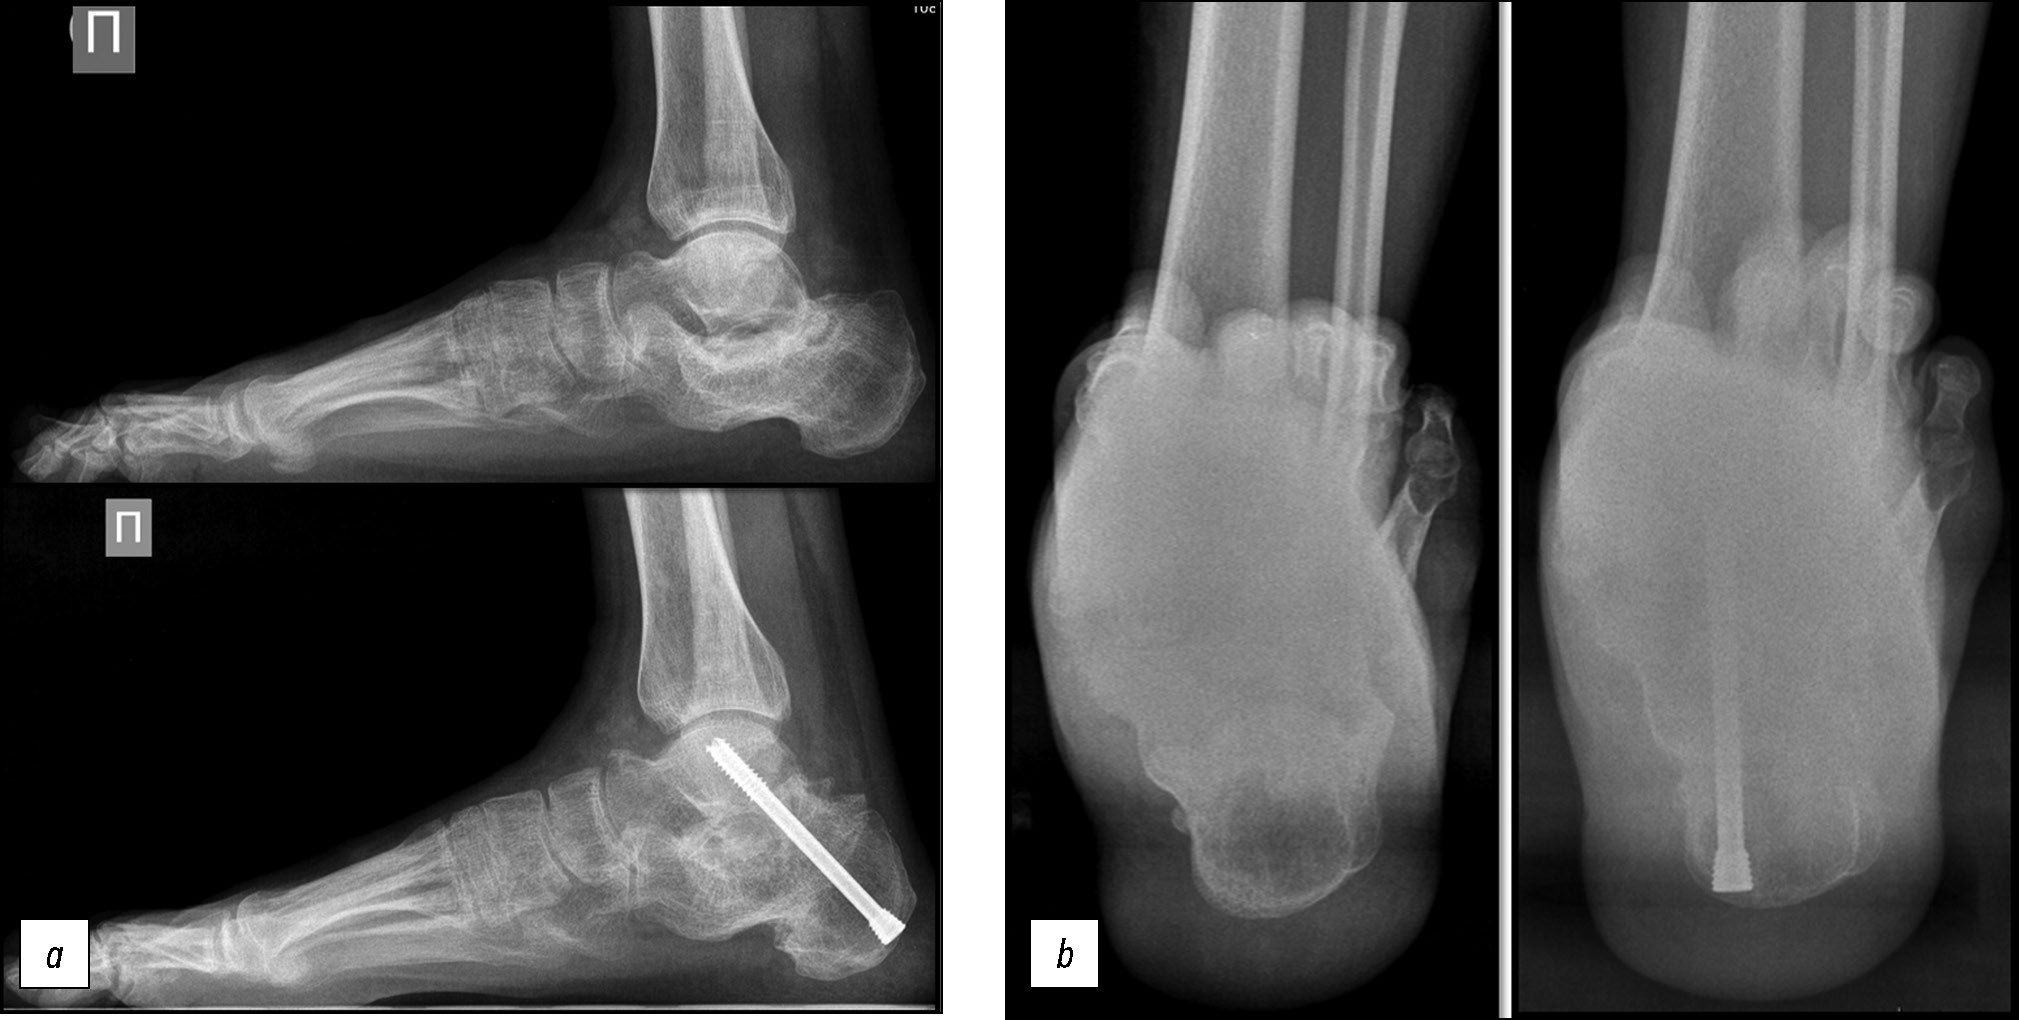

Представлен результат лечения пациента М., 31 года, в анамнезе кататравма, лечение консервативное, гипсовая иммобилизация. Через 11 мес. после травмы пациенту выполнена операция в следующем объёме: (1) удлинение правого ахиллова сухожилия по Страйеру; (2) краевая резекция наружной стенки пяточной кости, декомпрессия малоберцовых сухожилий; (3) корригирующая остеотомия правой пяточной кости с низведением; (4) дистракционный артродез подтаранного сустава, металлоостеосинтез; (5) тенотомия короткого сгибателя второго-пятого пальцев; (6) мини-инвазивная остеотомия проксимальной фаланги четвёртого-пятого пальцев (рис. 7).

Рис. 7. Рентгенограммы пациента М. в боковой проекции (a) и проекции Зальцмана (b) до операции и через 12 мес. после неё.

Fig. 7. X-ray of patient M. in the lateral (a) and Saltzman projection (b) before surgery and 12 months after it.